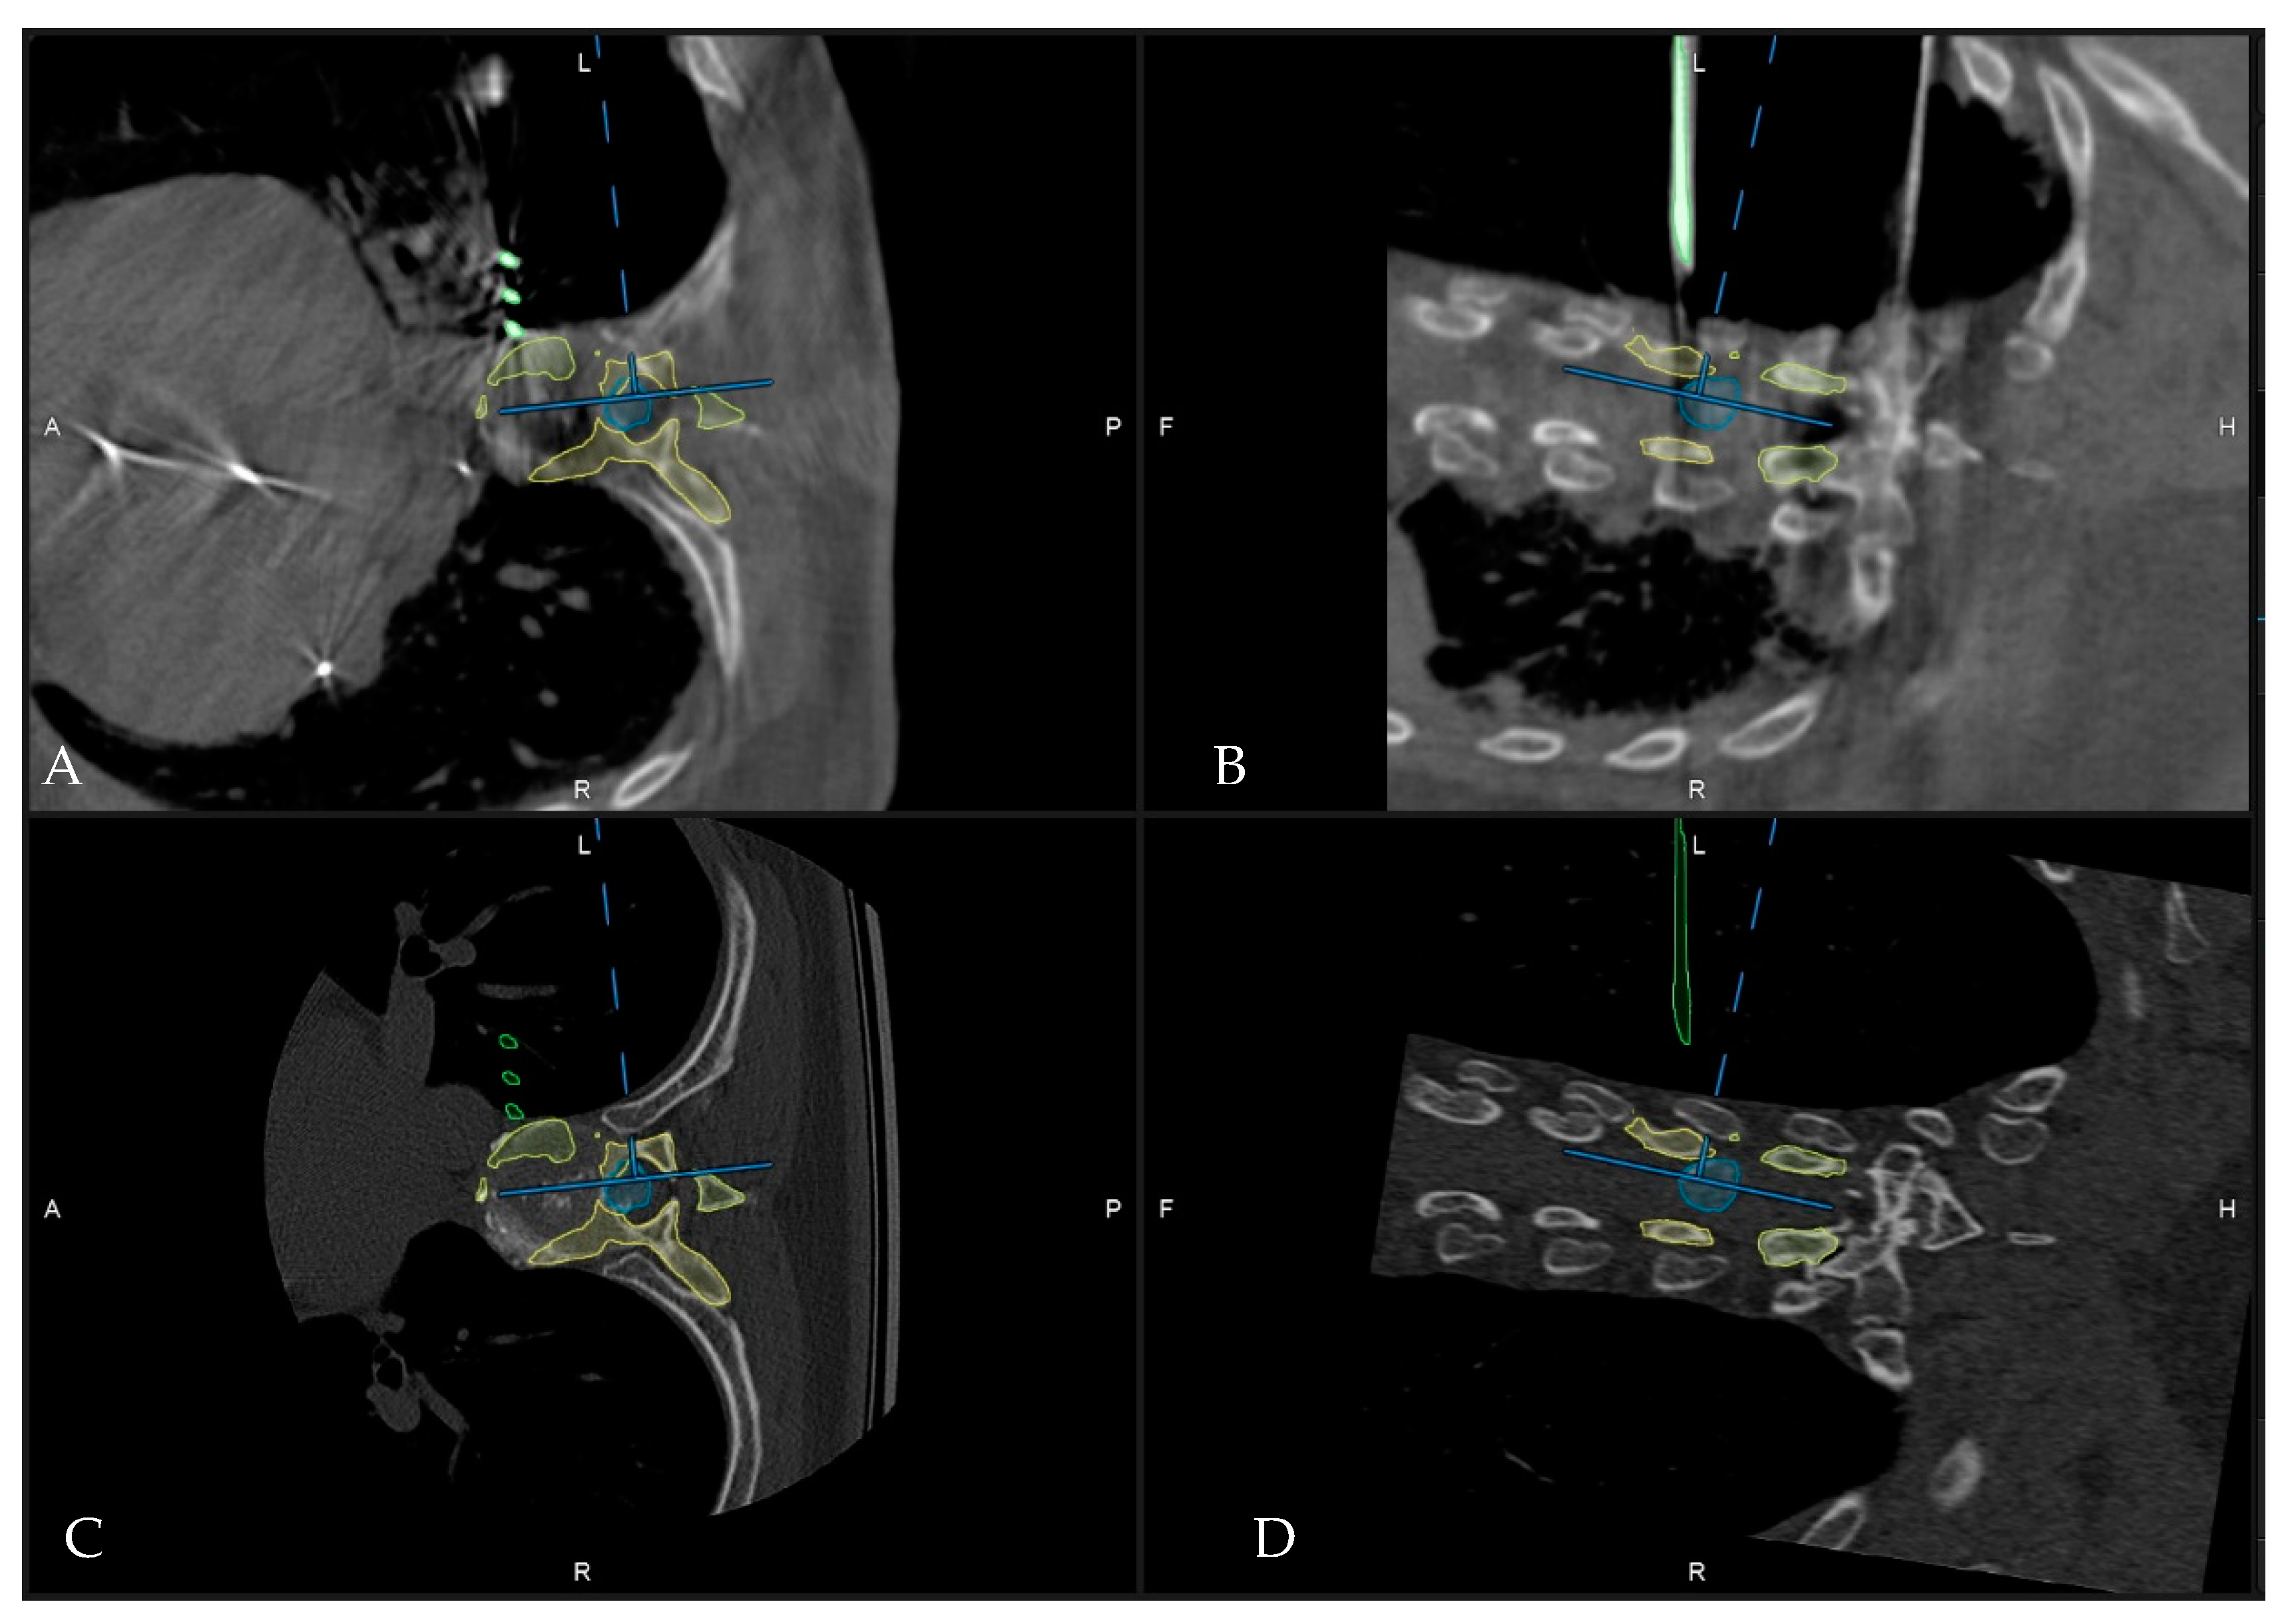

4. Patients